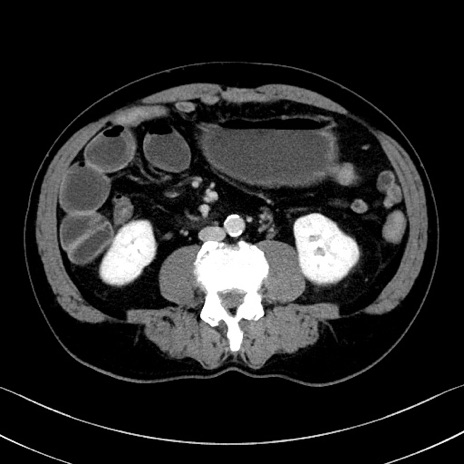

冠状断像